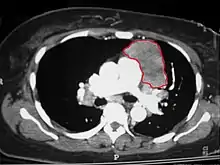

When a thymoma is suspected, a CT/CAT scan is generally performed to estimate the size and extent of the tumor, and the lesion is sampled with a CT-guided needle biopsy. Increased vascular enhancement on CT scans can be indicative of malignancy, as can be pleural deposits.[3] Limited biopsies are associated with a very small risk of pneumomediastinum or mediastinitis and an even-lower risk of damaging the heart or large blood vessels. Sometimes thymoma metastasize for instance to the abdomen.[5]

An encapsulated cystic thymoma.

A locally invasive circumscribed thymoma (mixed lymphocytic and epithelial, mixed polygonal and spindle).